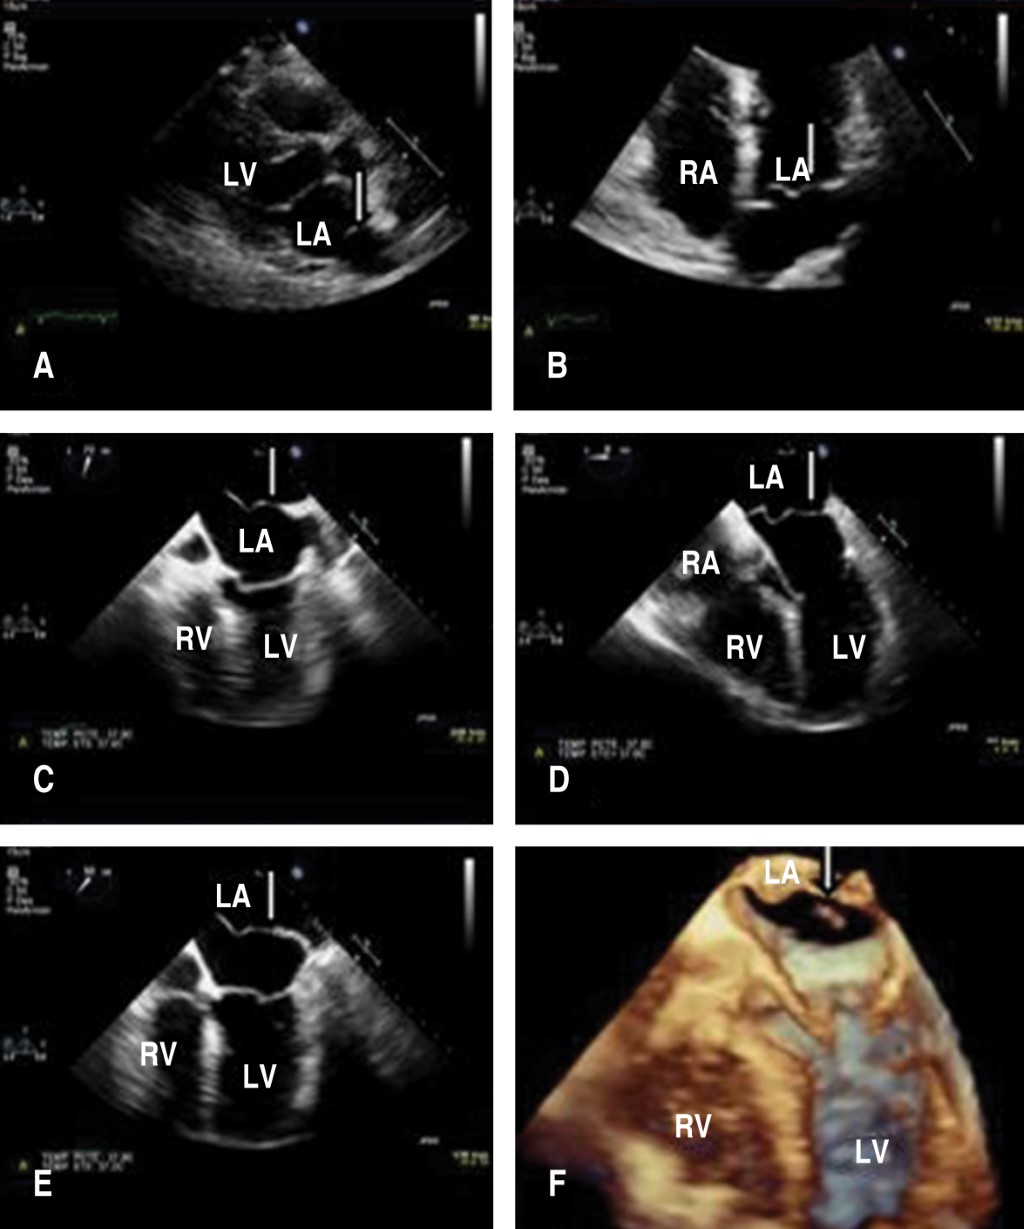

Caso clínico de Cor triatriatum en un paciente con fibrilación auricular CHA2DS2VASc de 1 punto

El Cor triatriatum sinistrum (CTS) es una anomalía cardíaca congénita rara con una incidencia del 0.1% del total de las cardiopatías congénitas y aún más infrecuente es su hallazgo en la edad adulta; se caracteriza por presentar una aurícula izquierda dividida en dos cámaras por una membrana fibromuscular que puede presentar o no fenestraciones. Se ha informado que la obstrucción grave está indicada por una velocidad Doppler máxima superior a 2 m/s o una presión transmembrana > 10 mmHg. En este artículo presentamos el caso de un paciente masculino de 68 años, quien presenta episodio de fibrilación auricular de novo en el contexto de cuadro infeccioso, con ecocardiograma transesofágico que evidencia CTS, con un puntaje de CHA2DS2VASc 1 punto, generando la interrogante si debía ser anticoagulado, dado que la evidencia en este tema es limitada, finalmente tomando la decisión de anticoagulación con DOACS.

Figura 1

Figura 2

Figura 3

Figura 4